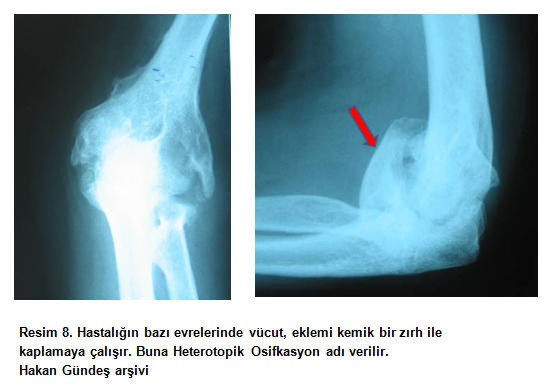

2)İntrensek: Eklem içi problem mevcuttur. Yani yanlış pozisyonda kaynamış kırıklar, eklem içi yapışıklıklar, eklemde dizilim bozukluğu (malalignment), eklem kıkırdak kaybı gibi bulgulardan en az biri mevcuttur. Direkt radyografi (filmler) normal değildir (resim 4, resim 5, resim 6).